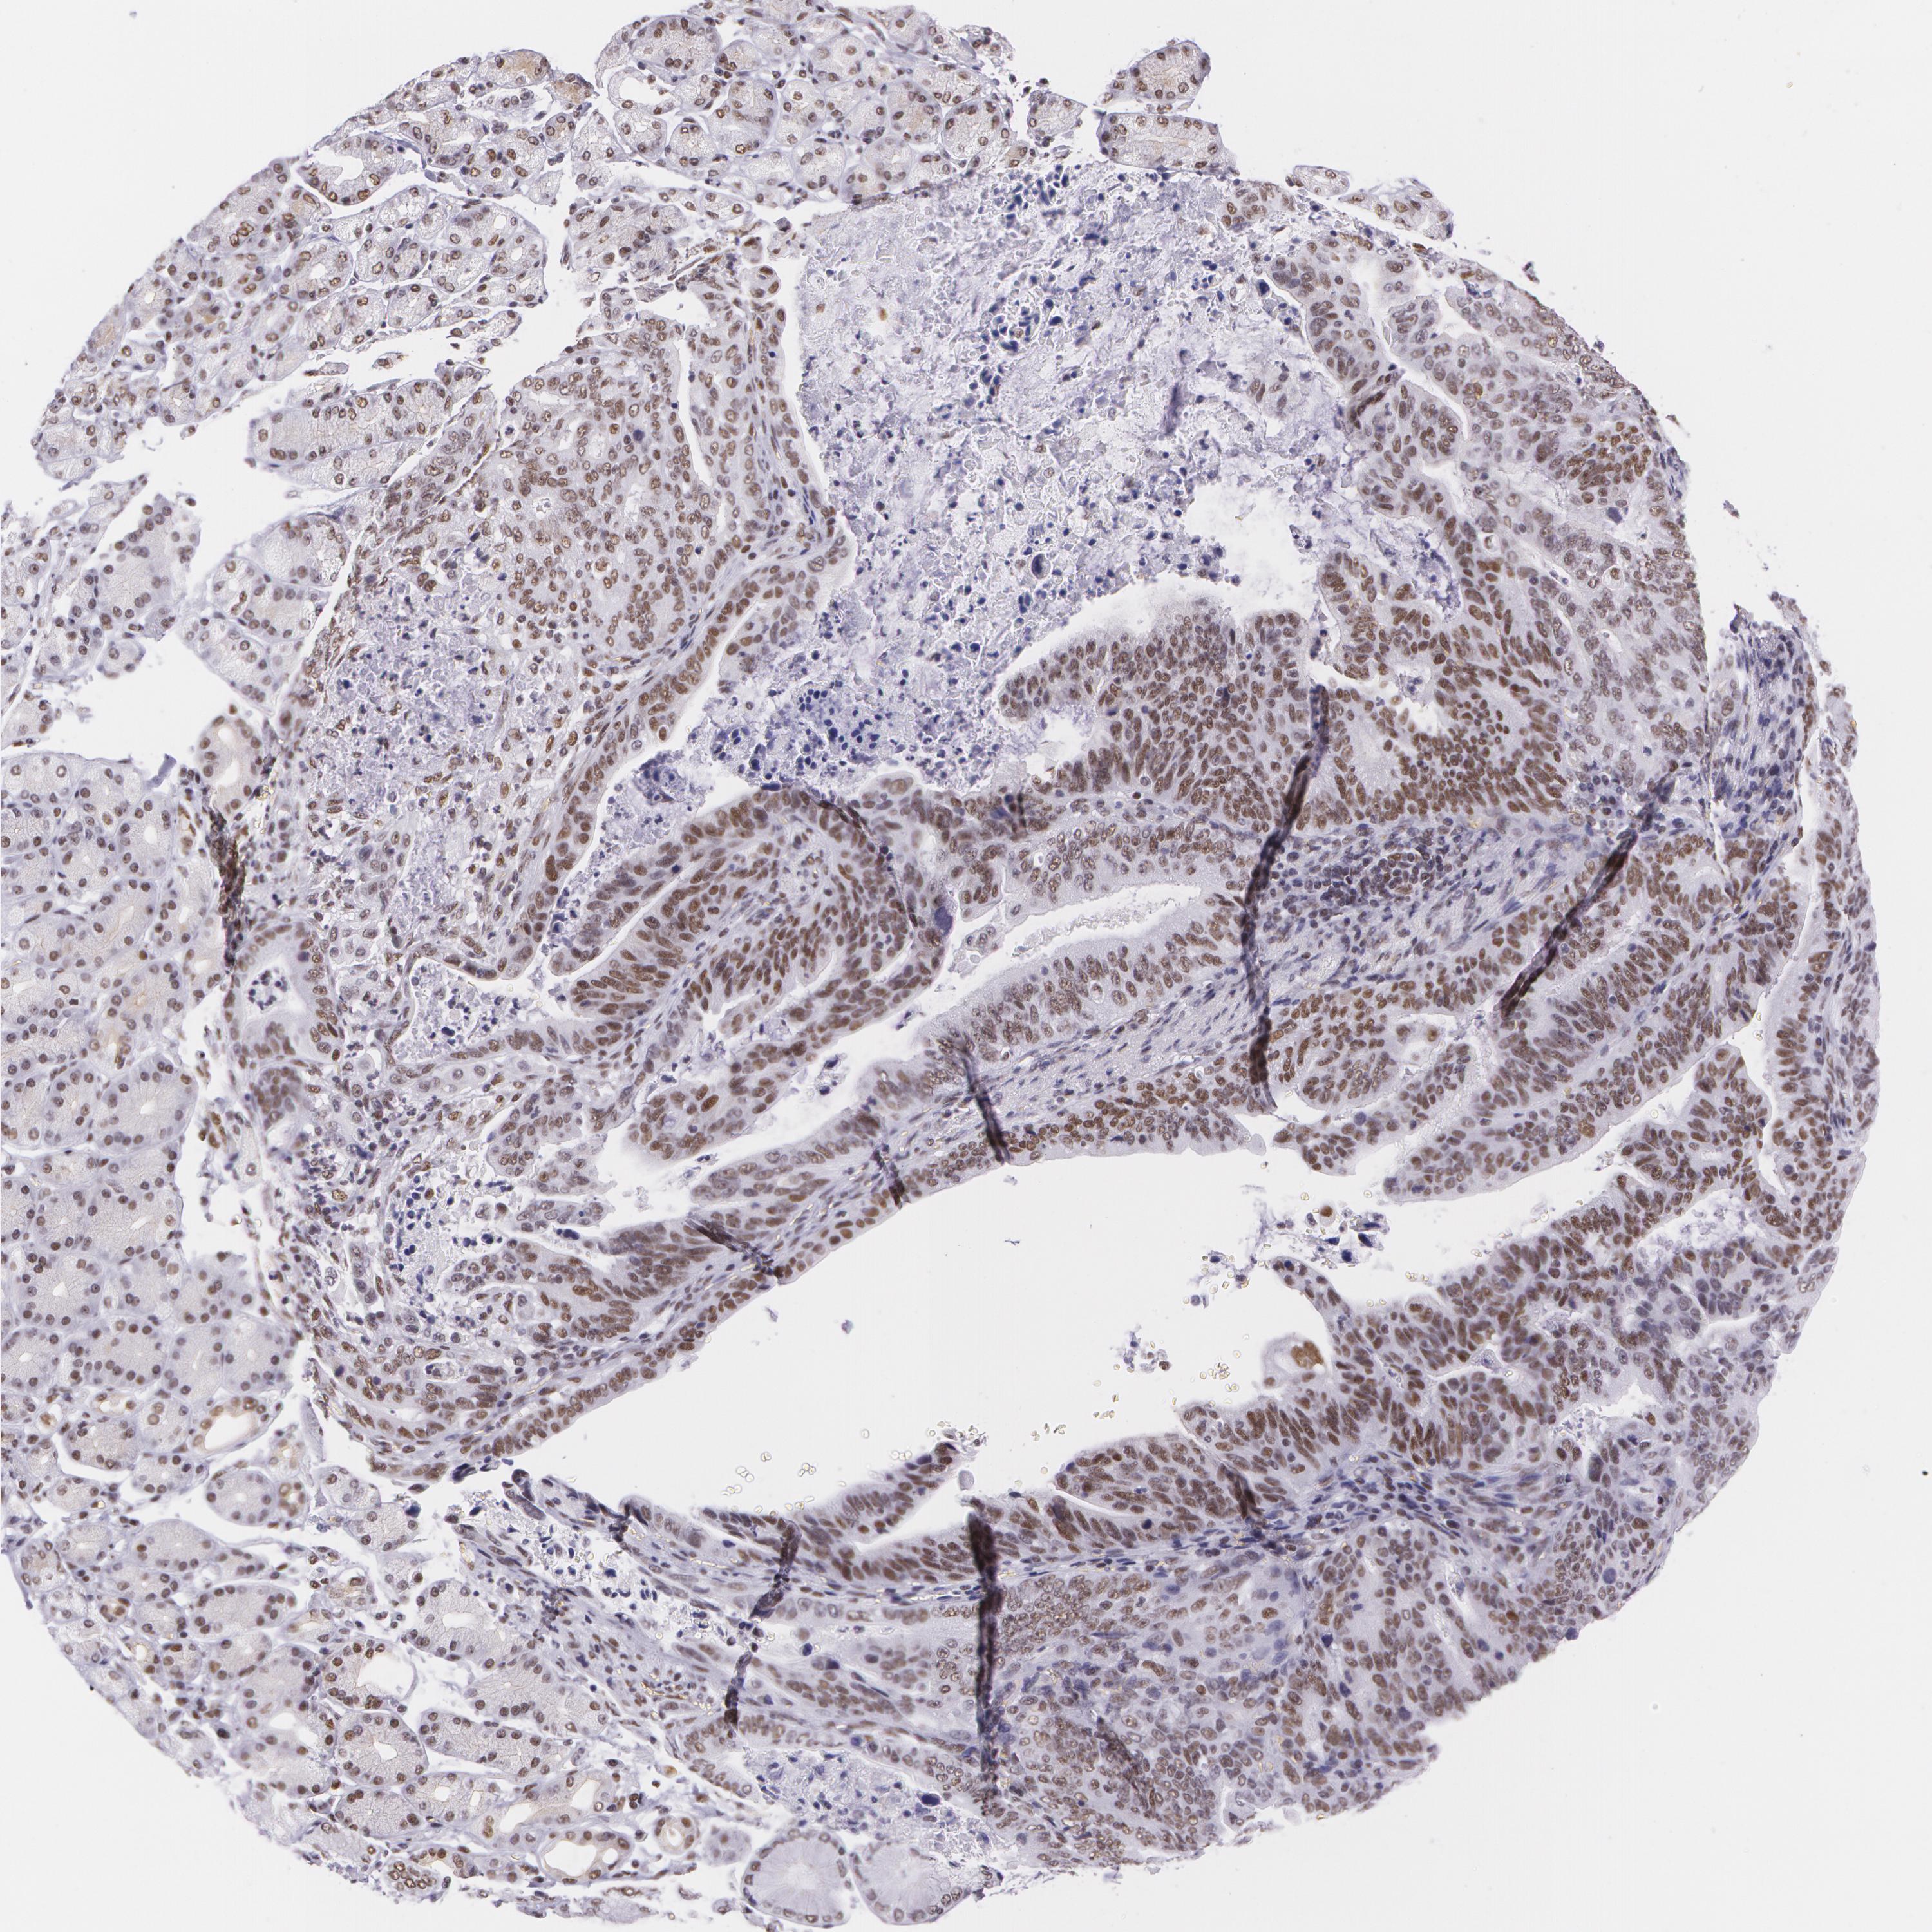

STOMACH CANCER - Protein expressioni

A mouse-over function shows sample information and annotation data. Click on an image to view it in a full screen mode. Samples can be filtered based on level of antibody staining by selecting one or several of the following categories: high, medium, low and not detected. The assay and annotation is described here.

Note that samples used for immunohistochemistry by the Human Protein Atlas do not correspond to samples in the TCGA dataset.

Antibody stainingi

Antibody staining in the annotated cell types in the current human tissue is reported as not detected, low, medium, or high, based on conventional immunohistochemistry profiling in selected tissues. This score is based on the combination of the staining intensity and fraction of stained cells.

Each image is clickable and will lead to virtual microscopy that enables deeper exploration of all samples and also displays staining intensity scores, fraction scores and subcellular localization as well as patient and tissue information for each sample.

Antibody HPA001429

Antibody CAB003836

Antibody CAB080233

Staining

High

Medium

Low

Not detected

Intensity

Strong

Moderate

Weak

Negative

Quantity

>75%

75%-25%

<25%

None

Location

Nuclear

Cytoplasmic/membranous

Cytoplasmic/membranous,nuclear

Adenocarcinoma, NOS

Adenocarcinoma, High grade